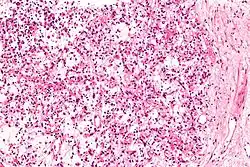

| Micrograph of an inflammatory myofibroblastic tumour of the kidney. Kidney biopsy. H&E stain. | |